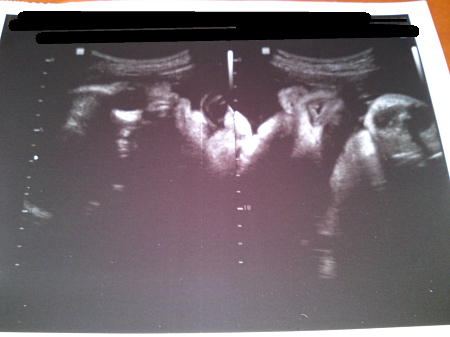

今週のエコー写真です。

左側は顔正面。

右側は顔をしたから見たところ、

鼻の穴と、少し開いた唇がわかりますかね~?

ちょうどお口をあけるところ、エコーで見れました。